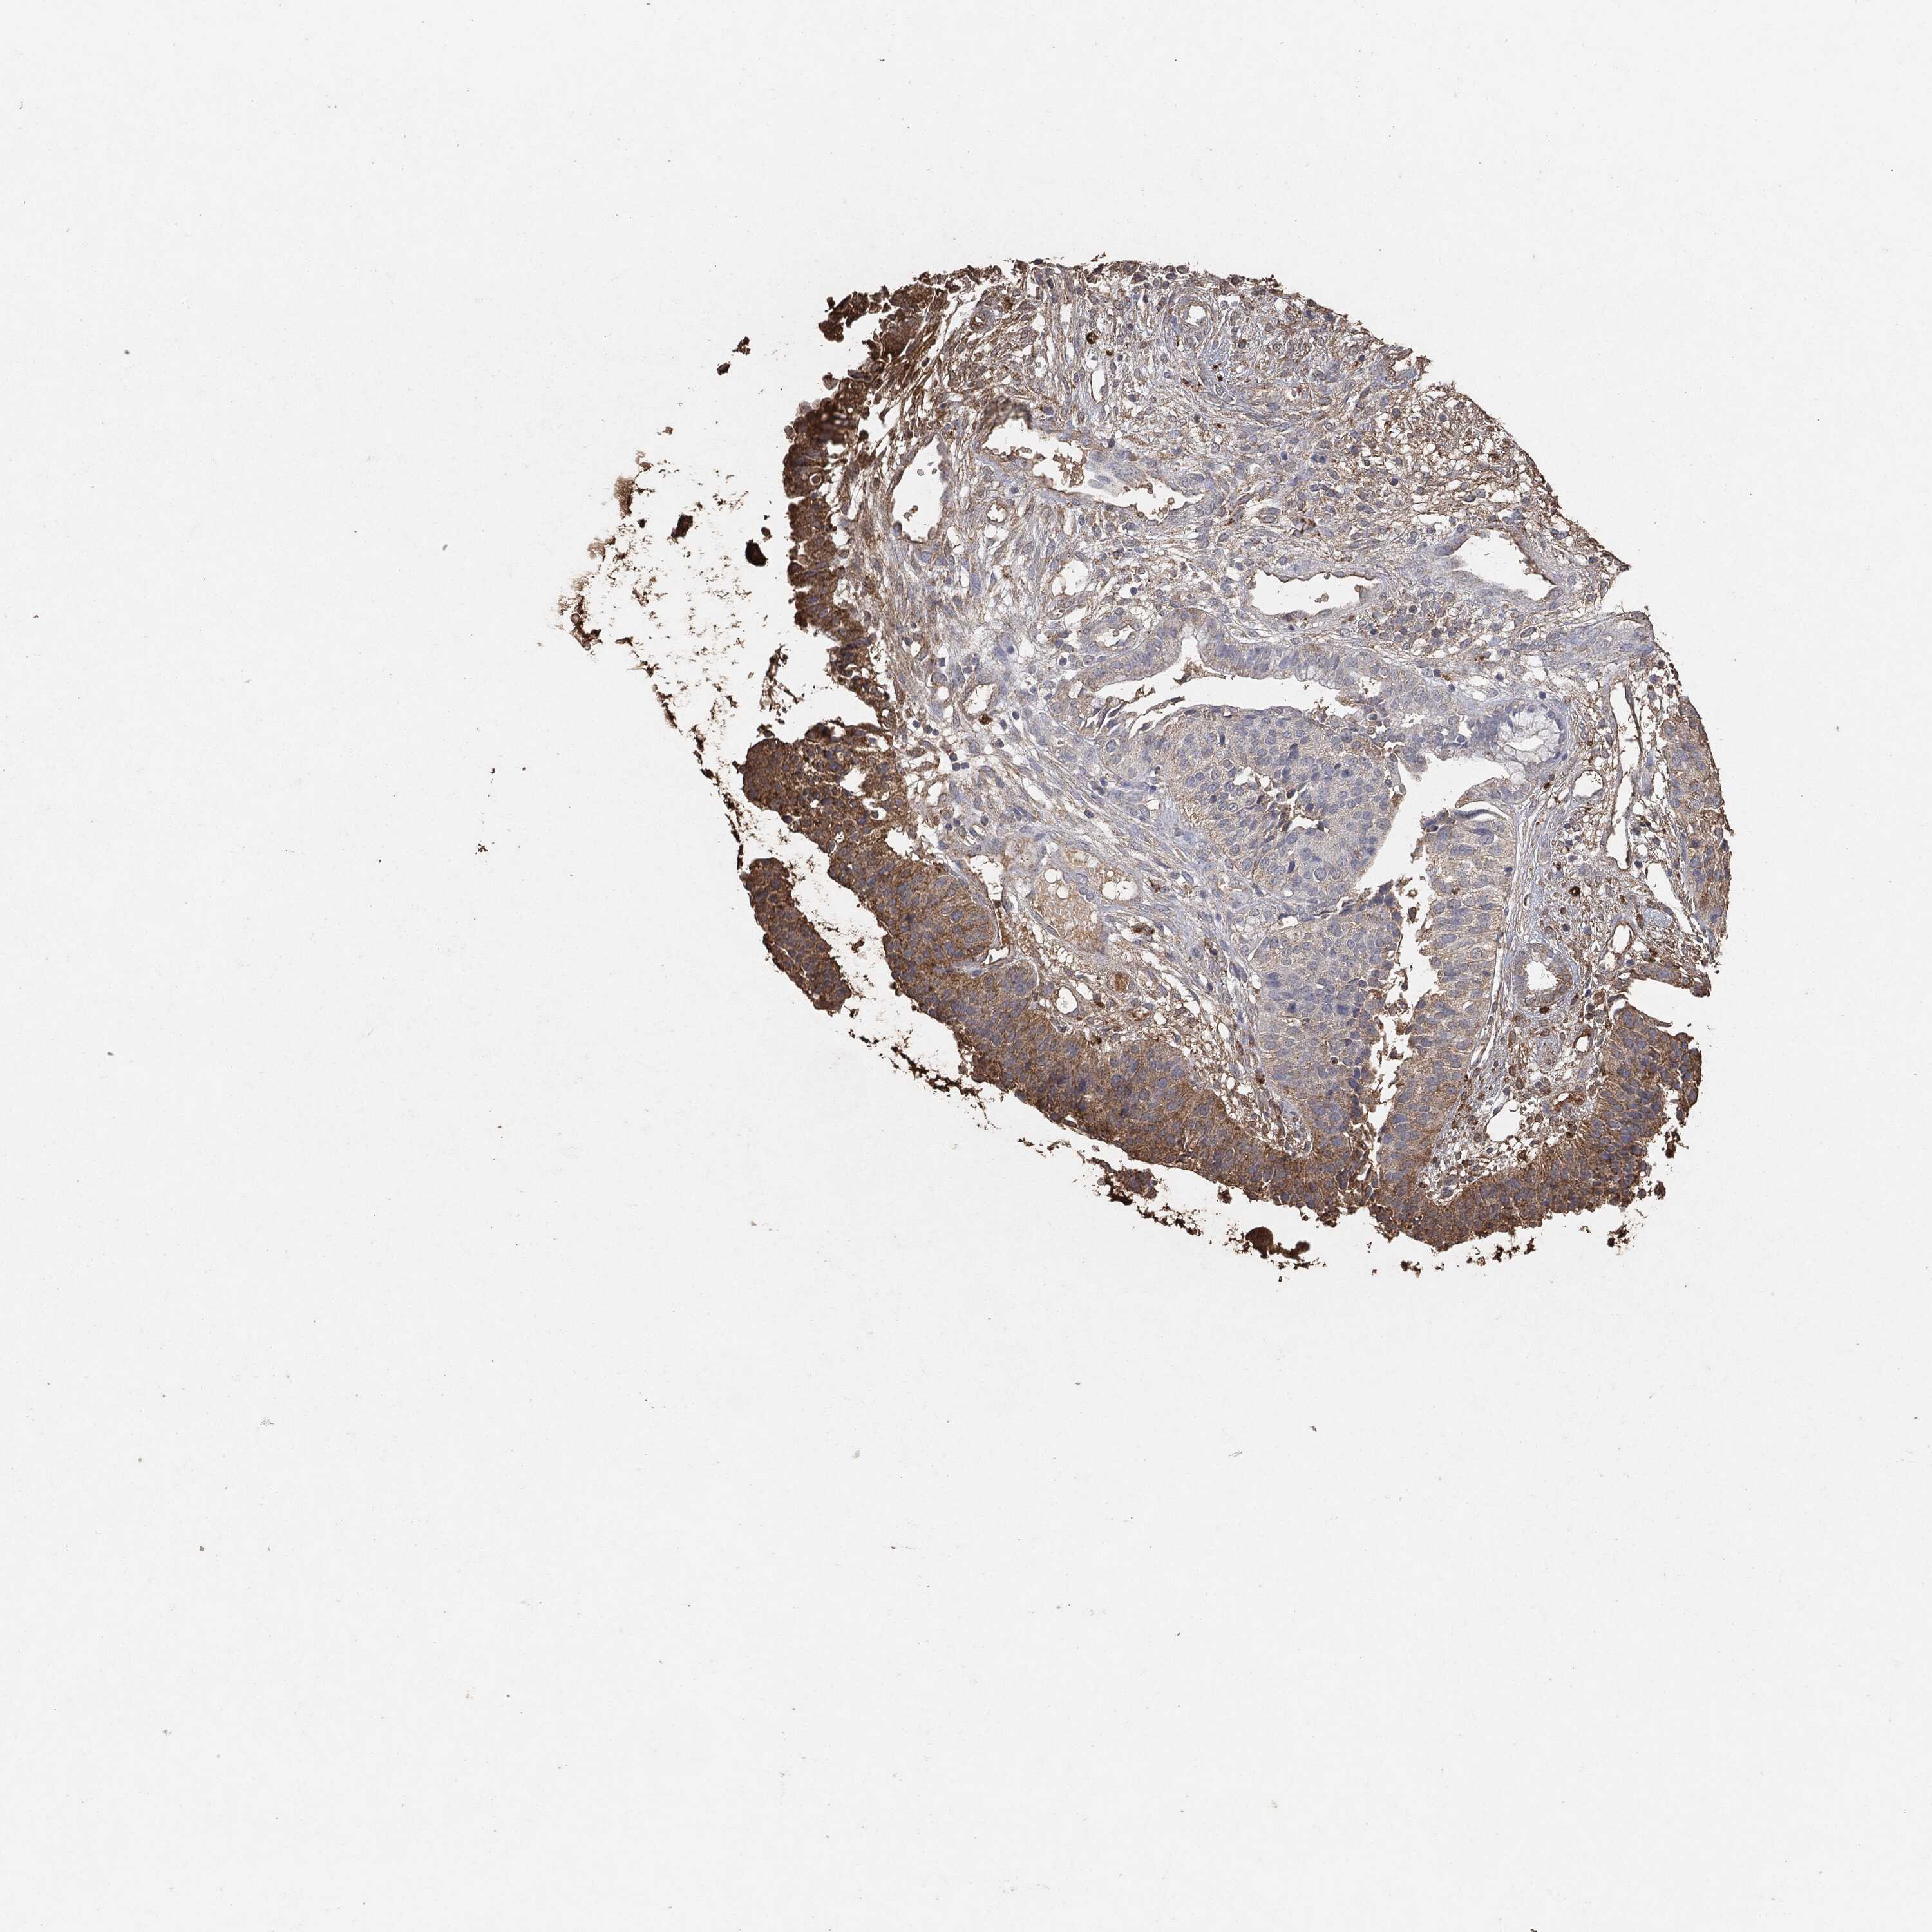

CERVICAL CANCER - Protein expressioni

A mouse-over function shows sample information and annotation data. Click on an image to view it in a full screen mode. Samples can be filtered based on level of antibody staining by selecting one or several of the following categories: high, medium, low and not detected. The assay and annotation is described here.

Note that samples used for immunohistochemistry by the Human Protein Atlas do not correspond to samples in the TCGA dataset.

Antibody stainingi

Antibody staining in the annotated cell types in the current human tissue is reported as not detected, low, medium, or high, based on conventional immunohistochemistry profiling in selected tissues. This score is based on the combination of the staining intensity and fraction of stained cells.

Each image is clickable and will lead to virtual microscopy that enables deeper exploration of all samples and also displays staining intensity scores, fraction scores and subcellular localization as well as patient and tissue information for each sample.

Adenocarcinoma, NOS

Squamous cell carcinoma, NOS